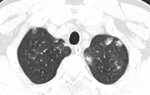

1.7. Ung thư phổi

Ung thư phổi có thể gây đau ngực khi ho kéo dài cùng các triệu chứng khác bao gồm giảm cân bất thường, mệt mỏi, thở hụt hơi, khàn tiếng, ăn mất ngon, cảm thấy mất sức, yếu.

2.2. Viêm phổi

Viêm phổi là một bệnh nhiễm trùng phổi do virus, vi khuẩn, nấm hoặc các chất khác xâm nhập vào phổi của bạn. Bệnh viêm phổi có thể gây ra những biến chứng ở người có hệ miễn dịch yếu hoặc không có can thiệp kịp thời.

Tùy vào cách mà cơ thể phản ứng với tác nhân gây viêm phổi mà các triệu chứng viêm phổi có thể khác nhau ở mỗi người. Nhưng nhìn chung, nếu bị viêm phổi bạn có thể bị ho khó thở; ho có đờm màu xanh, vàng hoặc lẫn máu; sốt; đổ mồ hôi và ớn lạnh.